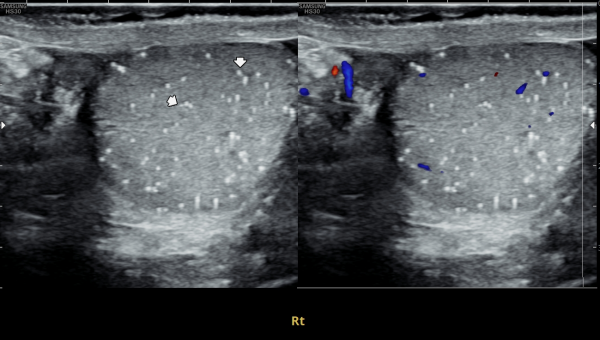

수년전부터 우측 고환의 통증으로 내원 당일 검사한 초음파 사진상 고환의 미석증이 관찰되는 사진입니다.(NIH:24)

The patient presented with right testicular pain for several years.

On the initial ultrasound examination performed on the day of the visit, the right testis shows multiple echogenic foci without acoustic shadowing, consistent with testicular microlithiasis.(NIH:24)

주 2회 14주 동안 정관과 사정관, 정낭 그리고 전립선의 표적 치료후 치료되고 있는 우측 고환 미석증들의 초음파사진입니다.(NIH:13)

This ultrasound image shows improvement of right testicular microlithiasis after targeted treatment of the vas deferens, ejaculatory ducts, seminal vesicles, and prostate.

The treatment was performed twice a week over a period of 14 weeks, and the previously observed tiny calcifications in the testis are gradually improving, suggesting better circulation and recovery of the reproductive tract.(NIH:13)